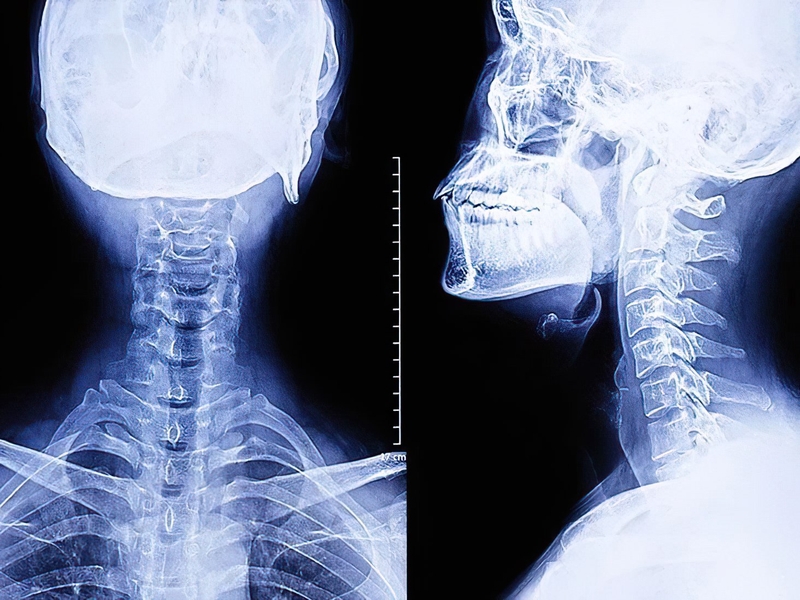

Chụp X quang tai mũi họng cũng bao gồm chụp X quang tai - xương chũm. Kỹ thuật này được áp dụng khi bác sĩ muốn xác thực một chấn thương ở sọ não có thể gây viêm xương đá, vỡ xương đá, có khối u ở góc tiểu cầu não, viêm tai xương chũm.... Trong trường hợp này, bác sĩ chỉ định tư thế chụp X- quang Stenvers. Lúc này, người bệnh cần nằm sấp cho đầu tựa vào bàn theo bờ trên xương gò má, ổ mắt và mũi. Lúc này, đường thẳng đứng sẽ tạo một góc 45 độ so với mặt phẳng dọc đứng của sọ.

Chụp X quang họng - thanh quản giúp bác sĩ dễ dàng quan sát các túi mủ ở vùng trước cột sống, khu vực sau khí quản, dị vật đường ăn, ung thư thanh quản, viêm tắc thanh quản…